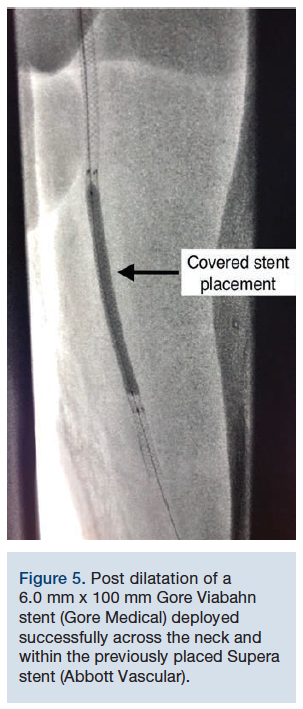

From the contralateral vascular access site, a 55 cm Raabe sheath (Cook Medical) was placed across the iliac bifurcation. An .018-inch Steelcore guidewire (Abbott Vascular) was advanced distal to the pseudoaneurysm and the decision was made to exclude it with a covered stent. A 6.0 mm x 100 mm Gore Viabahn stent (Gore Medical) was deployed successfully across the neck and within the previously placed Supera stent (Abbott Vascular) without complication. Post dilation was performed with excellent final angiographic results (Figures 5-6) showing patency of the SFA with successful exclusion of the pseudoaneurysm. The patient had immediate improvement in pain and was back to normal activity levels one week later. He was maintained on apixaban 5 milligrams twice a day and clopidogrel 75 milligrams daily.